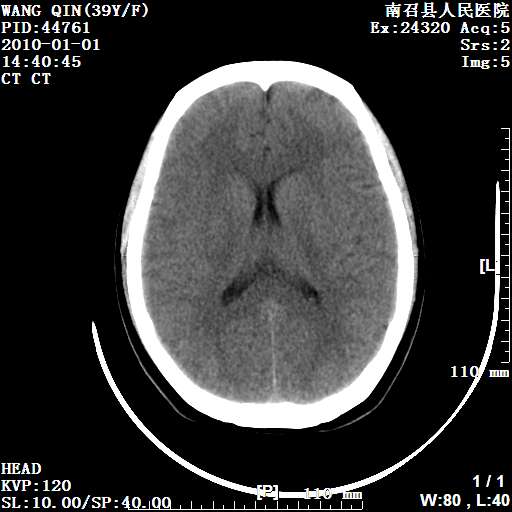

以下是引用随光逐影在2010-1-22 9:03:00的发言:[br]考虑左侧中颅窝(蝶骨翼区)脑膜瘤侵犯蝶骨翼并突入左侧眼眶。

以下是引用水过无痕在2010-1-22 14:55:00的发言:[br]一、定位:颅外占位;二、定性:恶性可能性大;三、组织来源:来源于左侧眼外直肌或其他部位;考虑为:横纹肌肉瘤>转移瘤>脑膜瘤.